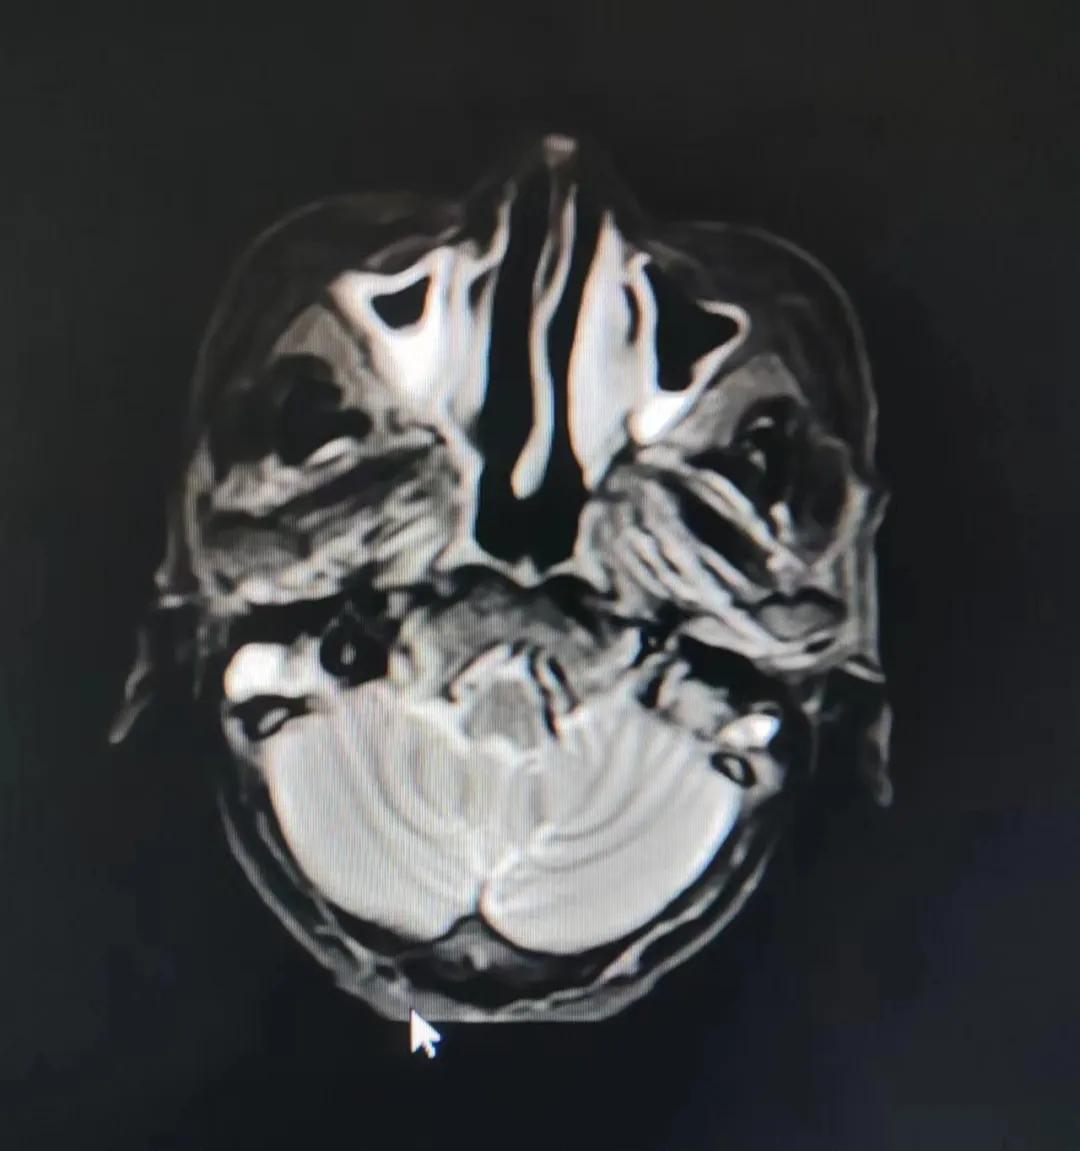

治療前

考慮到患者年齡較大、體質(zhì)差,手術(shù)難度大,且常規(guī)的放射治療難以保護(hù)患者晶體造成患者雙眼視力損傷,放療團(tuán)隊(duì)以最快的速度制定了精準(zhǔn)放射治療方案并開(kāi)始為其實(shí)施治療。僅僅數(shù)日后,老人腫塊出血即得到控制,腫塊明顯縮小,放療20次后腫塊迅速縮?。?/div>

治療后

放療結(jié)束,除了放療處的皮膚輕微放射性皮炎外,基本沒(méi)有什么不良反應(yīng)。復(fù)查發(fā)現(xiàn),鼻腔淋巴瘤已不可見(jiàn),目前患者已康復(fù)出院。